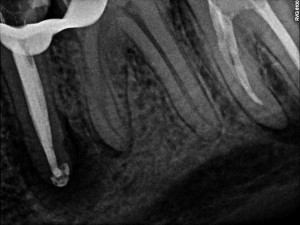

Drugi przedtrzonowiec w żuchwie uratowany. W wyniku terapii endodontycznej nastąpił całkowity zanik zmiany zapalnej w rejonie drugiego przedtrzonowca w żuchwie po lewej stronie. Leczenie kanałowe z użyciem mikroskopu była dodatkowo utrudniona ze względu na pacjenta i jego odruch refluksu. Pacjent zgłosił się do placówki NZOZ Stomatologia Bez Bólu bardzo narzekając na ból, jak określił nie do wytrzymania w żuchwie po lewej stronie. Podczas badania radiologicznego OPG i RVG stwierdzono dużą zmianę zapalną w okolicach wierzchołka korzenia drugiego przedtrzonowca w żuchwie po lewej stronie, generującą zanik kość w tym sektorze żuchwy.

Kanał wypełniono za pomocą Obtury i Systemu B ciekłą gutaperką z użyciem sealera AH+.